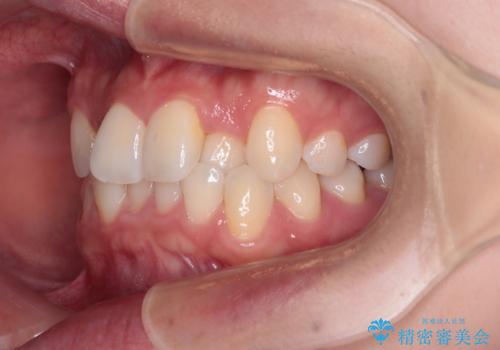

前歯のクロスバイト 裏側に隠れた歯をワイヤー装置で短期間治療

- 上顎前歯のクロスバイトを気にして来院された患者様です。

ワイヤー矯正でもマウスピース矯正でも対応可能でしたが、マウスピースによる自己管理に一切の自信がないとのことで、ワイヤー装置にて矯正治療を行うこととしました。

装置の外見を気にしていましたが、短期間で治療を終えることができるだろうと伝えると、安価であるメタルブラケットを選択されました。

想定通り、1年強で綺麗に仕上げることができました。